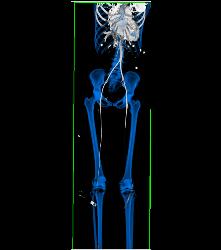

CTA Runoff With Occluded Left Popliteal Artery